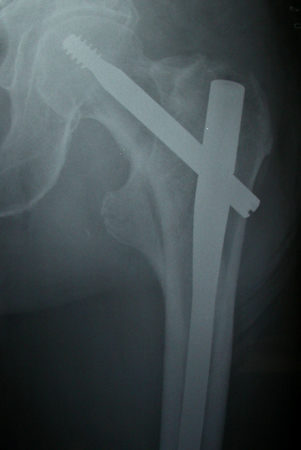

Con los tipos de fractura extracapsulares, la estabilidad de las fracturas desplazadas generalmente tiene en cuenta el grado de conminución y, más específicamente, la conminución de la corteza medial. Los tipos de fracturas intertrocantéricas simples de 2 fragmentos sin conminución del calcar medial (corteza) generalmente se consideran estables. Las fracturas intertrocantéricas de 3 y 4 fragmentos con ruptura de la corteza posteromedial o la fractura con oblicuidad invertida se consideran inestables.[3][51][Figure caption and citation for the preceding image starts]: Radiografía anteroposterior inicial que muestra una fractura intracapsular de la cadera izquierda desplazadaDe la colección de Bradley A. Petrisor, MSc, MD, FRCSC y de Mohit Bhandari, MD, MSc, FRCSC [Citation ends].